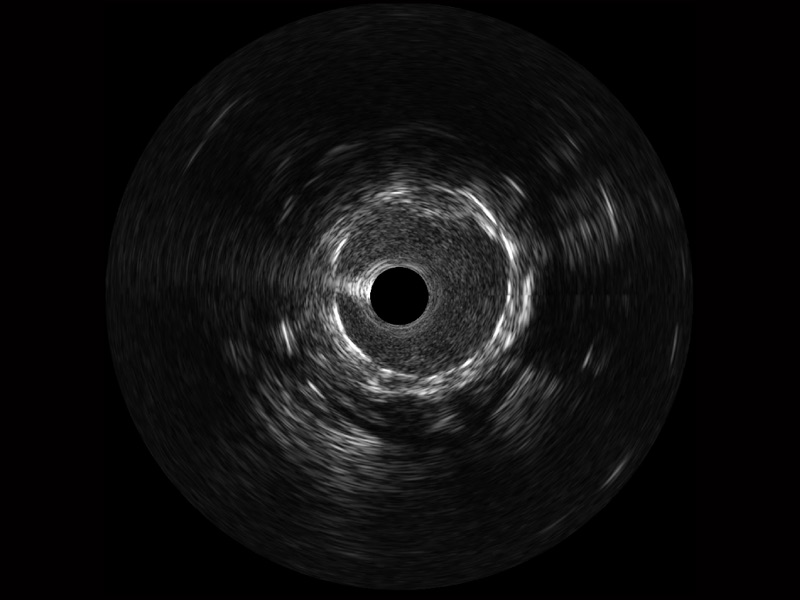

狗万官方网站宽频IVUS图像

传统IVUS图像

对比传统IVUS导管成像,狗万官方网站宽频IVUS图像的近场支架梁显影更细腻,远场中膜外血管仍清晰可辨,兼顾远中近,兼顾分辨力与穿透深度